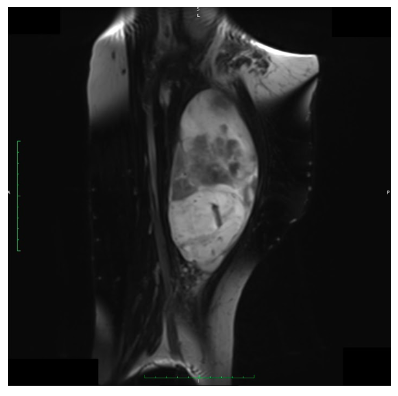

Radiographic imaging is used to help form a diagnosis. These include X-Ray, MRI, CT and Bone Scans.

An example of an MRI is shown.